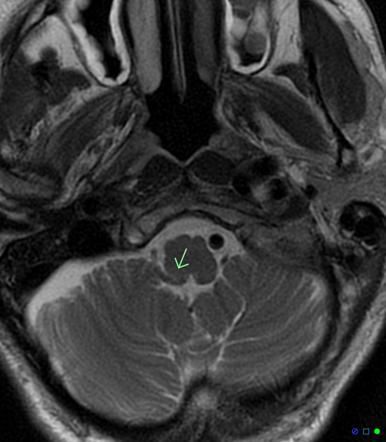

Posterior inferior cerebellar artery syndrome refers to the constellation of neurological symptoms attributed to lateral medullary injury. The condition is also known as a lateral medullary syndrome. Signs and symptoms of Wallenburg syndrome are: - Contralateral loss of pain and temperature sensations on trunk and extremities - Ipsilateral loss of pain and temperature sensations on face - Dysphonia - Difficulty swallowing - Slurred speech - Nasal regurgitation - Palatal myoclonus - Vertigo - Ipsilateral vocal cord paresis The most common risk factor of posterior inferior cerebellar artery syndrome is hypertension. Trauma and collagen vascular disease can also implicate in wallenburg syndrome. The management of Wallenburg syndrome aims at relieving the symptoms and rehabilitation. Reference: https://medicine.uiowa.edu/iowaprotocols/wallenberg-syndrome-pica-syndrome-lateral-medullary-infarction#:~:text=Wallenberg%20syndrome%20%3D%20Lateral%20medullary%20syndrome,opposite%20side%20of%20the%20infarction Image via: https://radiopaedia.org/articles/lateral-medullary-syndrome